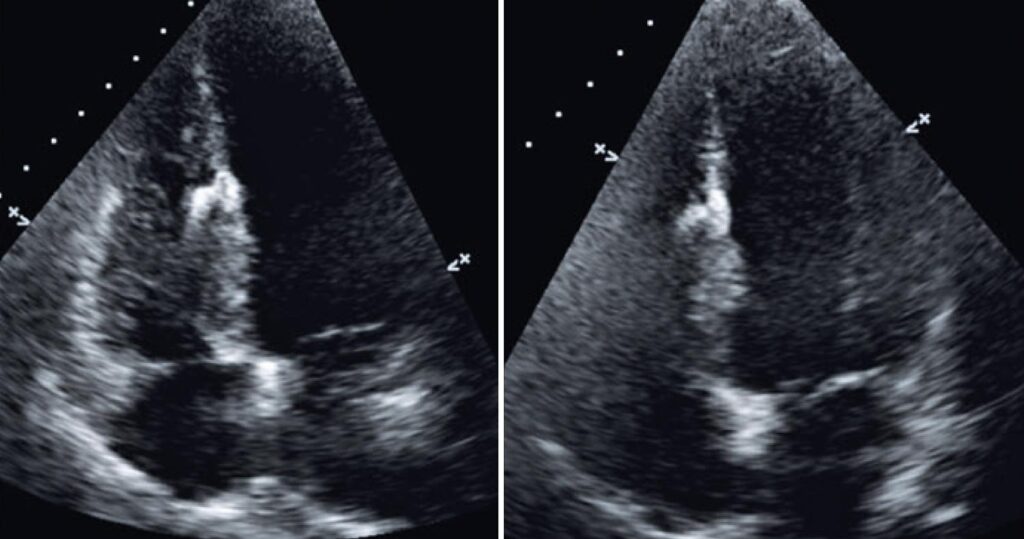

Figure 4

Transesophageal echocardiogram after the procedure showing a well-positioned prosthesis, with no signs of complications and no residual transseptal flow.